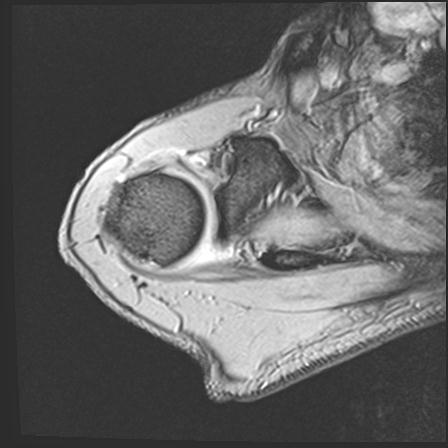

60058 3/9 11/4 右肩 2R+MRI 73歳男性 肩腱板損傷